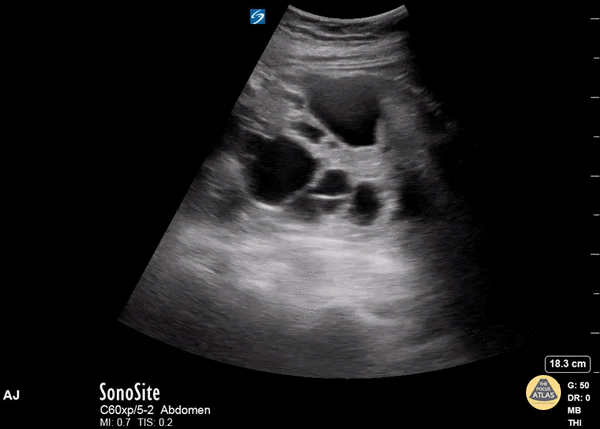

One Minute Image Review

One-Minute Image Review: High yield bite sized learning! Voice annotation of both normal and abnormal point of care ultrasound clips!